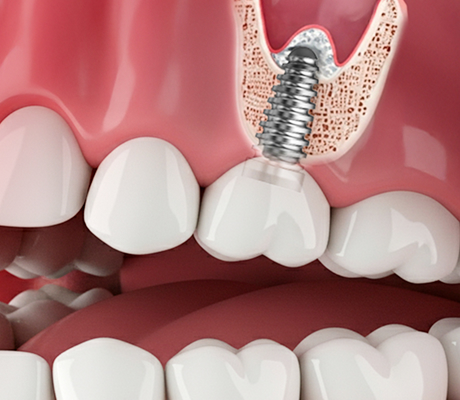

임플란트,

잃어버린 치아, 다시 찾는 자신감!

자연 치아가 빠진 자리에 인공 치아 뿌리를 심어 새 치아를 만드는 치료입니다.

틀니보다 단단하고, 진짜 치아처럼 편하게 씹을 수 있습니다.